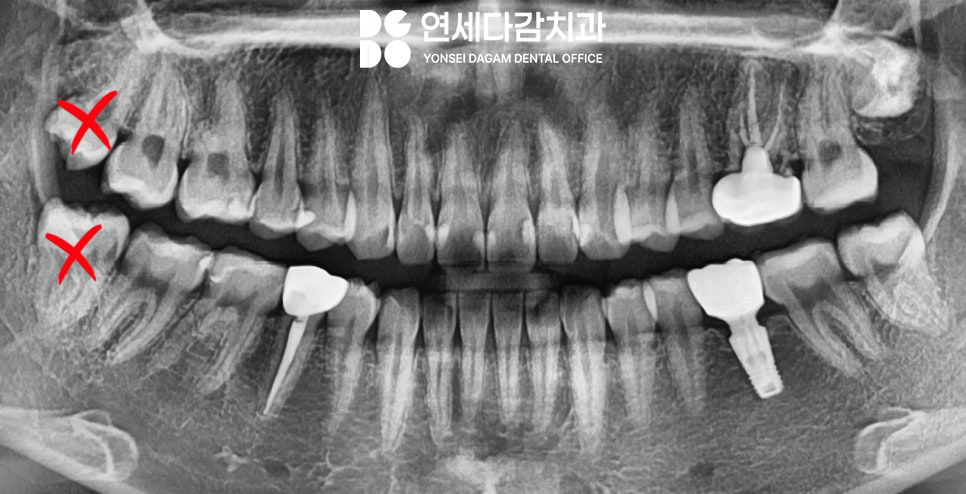

초진 엑스레이(2023.12.18)

오른쪽 아래 작은 어금니 부위에

매복 과잉치가 존재합니다.

(주로 파노라마에서 먼저 발견됩니다.)

*추후 위치 상 관리가 어렵던

오른쪽 위 아래 사랑니(#18,48번)도

함께 뽑았습니다.